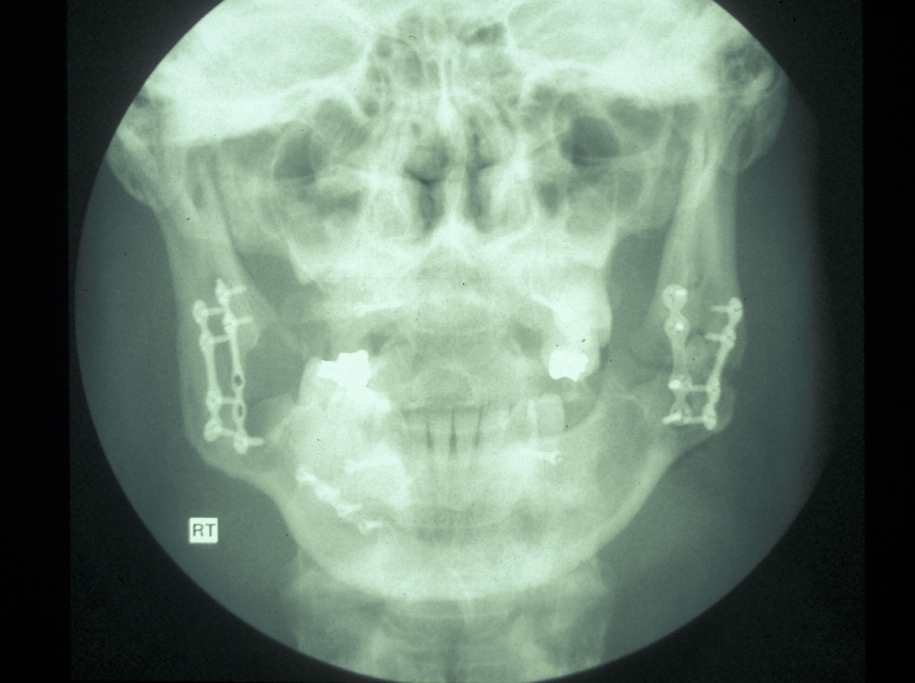

In the region of the angle of the mandible, a single plate is adequate to allow healing. In practice many surgeons now supplement this (or even replace it) with a transbuccally placed lateral plate which prevents lateral displacement of the lower border of the mandible. All these techniques use monocortically placed matching titanium screws to retain the plates which immobilise the fracture sites. Long-acting local anaesthetic regional block provides good postoperative analgesia and prophylactic broad-spectrum antibiotics are given preoperatively. Intraoral wounds are closed with resorbable sutures. If the occlusion is fully restored and stability of the fracture is assured by the plates, the intermaxillary fixation can be removed. Postoperative radiographs are taken to ensure correct placement of plates and screws and accurate realignment of mandibular fragments. It is also important to reassess the position of the condyles following ORIF as malpositioning can lead to TMJ problems later on (see Figure 5).

Condylar fractures: these are the most common mandibular fractures. They are treated conservatively in children up to 12 years with soft diet, analgesia and function. Young adults (12-18) are also treated conservatively in the majority of cases. Adults (>18) are treated with 7-10 days of heavy elastic IMF (fixation) and the occlusion reassessed. If malocclusion persists then ORIF of the condyle is undertaken. Overlap of fragments greater than 5 mm and angulation greater than 37°are postulated to warrant ORIF. Logically the function rather than the radiographic appearance should predicate the decision to undertake ORIF (see Figure 9 and Figure 10 for illustration).